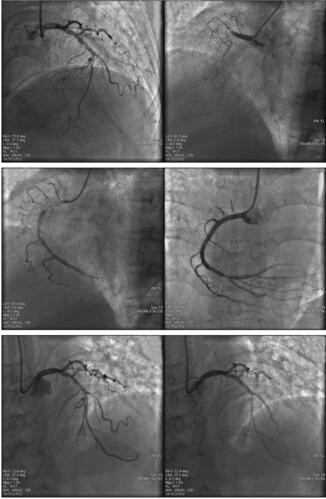

立即行临时起搏器置入术,设置起搏频率70次/分,予以高渗盐纠正低钠血症,BiPAP 呼吸机辅助呼吸;亚胺培南西司他丁钠1g,3次/日,静脉滴注;呋塞米利尿、多巴胺强心、硝酸甘油减轻后负荷;阿司匹林100mg,1次/日,口服;氯吡格雷75mg,1次/日,口服;低分子肝素钙5000U,2次/日,皮下注射;配合中药灌肠。患者入院12小时后恢复意识,未诉胸痛不适;3天后ECG 恢复窦性心律,电解质正常,双下肢水肿明显减轻,肺部湿性啰音消失,血气分析正常,患者可平卧位;7天后行PCI 术。术中见前降支中段弥漫性狭窄,中远段次全闭塞,对角支开口后弥漫性狭窄,回旋支散在斑块,未见明显狭窄,远端向右冠状动脉逆向供血,右冠状动脉开口后完全闭塞(图009‐2)。

图009‐2 造影结果

PCI 过程:右冠状动脉采用JR4.0GC,Pilot50GW 并以APEX 2﹒0mm×20mm 球囊加强支撑,将G W 送至右冠状动脉远端并预扩张后,由远及近依次释放Firebird 3﹒0mm×33mm、Firebir d 3﹒5mm×33 mm 支架;左冠状动脉采用EBU3.5GC,Pilot50GW 送至前降支远端,APEX 2﹒0mm×20mm 球囊预扩张后,送入Firebird 2﹒5mm×18mm 支架以10at m 释放,撤GW 于对角支,送入Firebird 2﹒5mm×18mm 支架以8at m 释放。